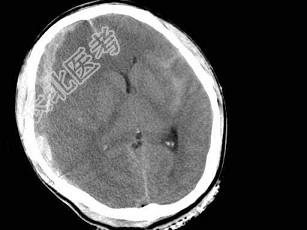

- 单项选择题男,38岁, 外伤后半个月,行CT复查如图, 最可能的诊断为 ( )

A、脑出血

B、硬膜外血肿

C、脑萎缩

D、脑挫裂伤

E、亚急性硬膜下血肿